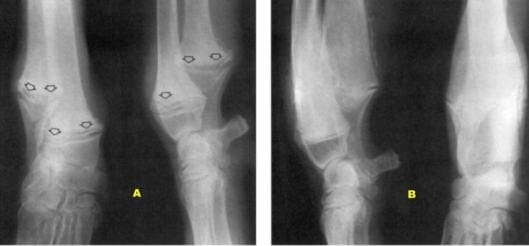

Un altro esempio: alano femmina di 5 mesi. Da tre giorni aveva difficoltà a muoversi. Le metafisi distali di radio e ulna e le zone meta-epifisarie delle tibie apparivano tumefatte. Vennero eseguiti gli esami radiografici.

A: carpo destro. Nella parte prossimale l’articolazione rivela tumefazione dei tessuti molli. Le zone meta-epifisarie di radio e ulna sono allargate. I confini periostali sono irregolari. Una linea radiolucente (frecce) è in posizione immediatamente prossimale alle piastra epifisarie delle due ossa. Prossimalmente a questa, una seconda linea sclerotica. La zona meta-epifisaria distale dell’ulna non ha più il normale disegno coniforme.

B: la radiografia ripresa due mesi più tardi evidenzia l’immutata situazione delle zone meta-epifisarie distali di radio e ulna. Il disegno dell’ossificazione entro il canale midollare è irregolare. La metafisi distale dell’ulna ha riacquistato il normale disegno coniforme. Le zone meta-epifisarie distali di radio e ulna sono interessate da reazione periostiale. Le fisi distali di radio e ulna sono nella norma, ma l’alterato accrescimento dell’arto ha residuato incurvamento e valgismo.

Diagnosi: osteodistrofia ipertrofica.